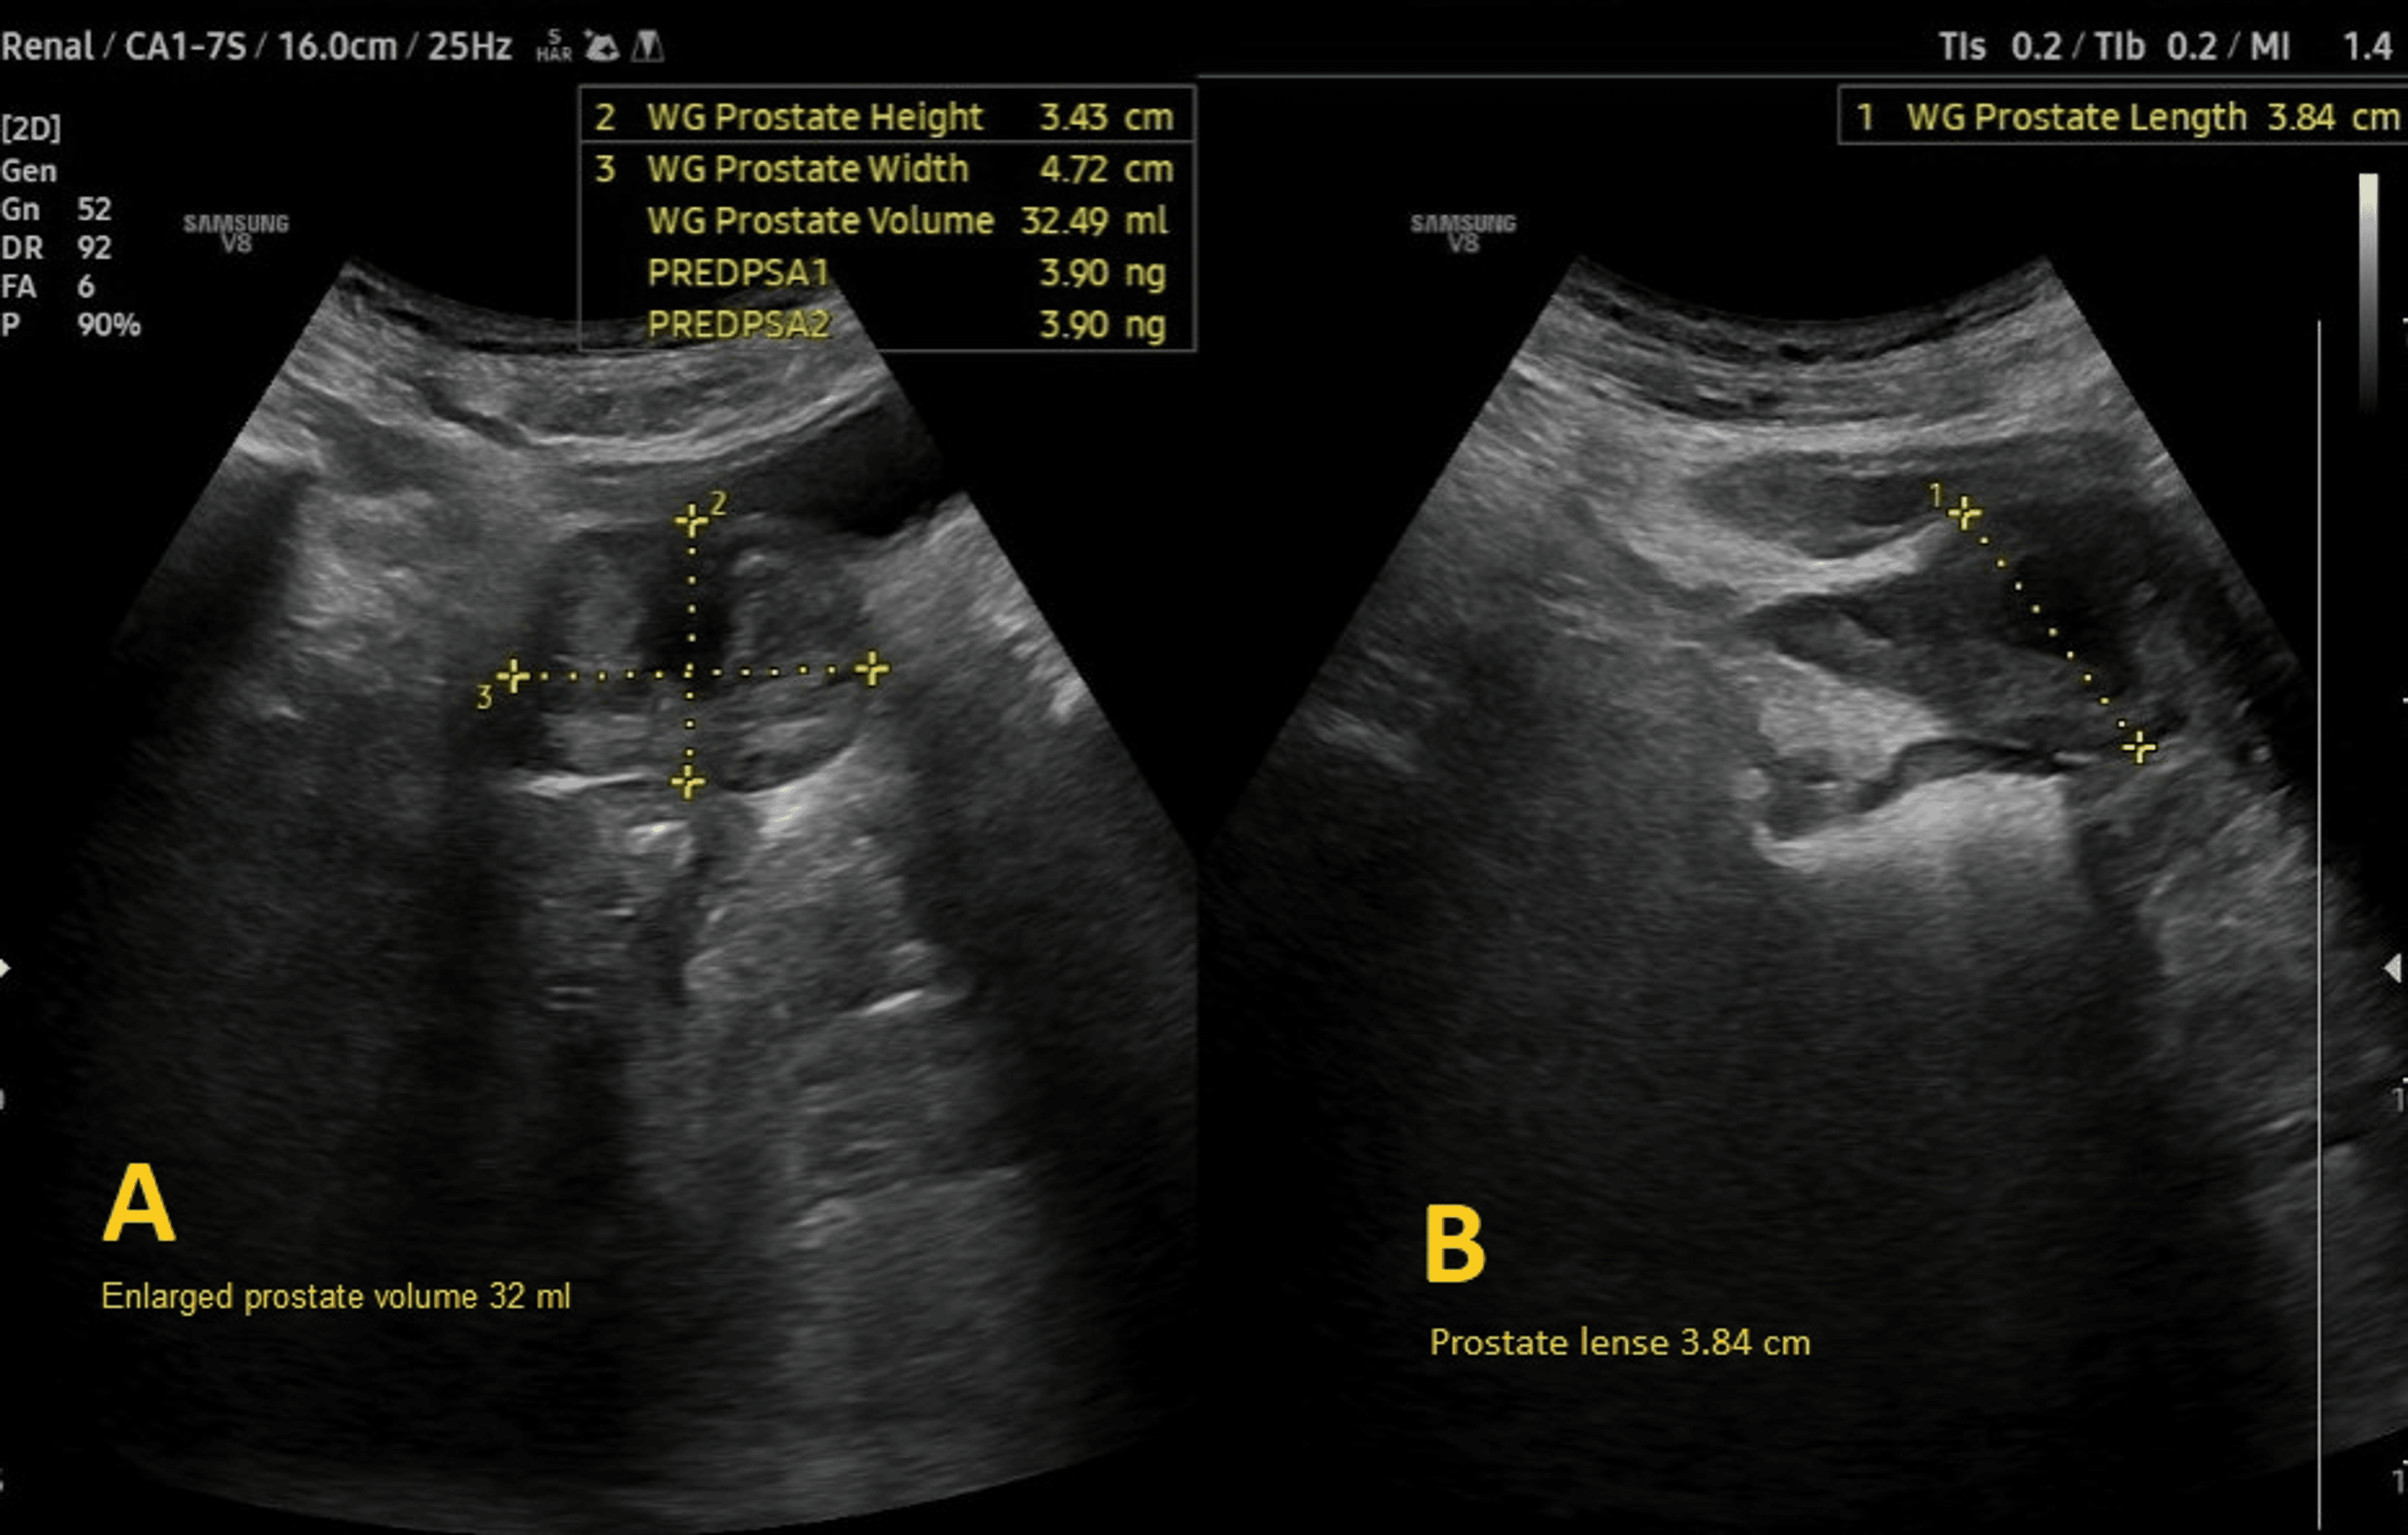

An 80-year-old male presented to the Emergency Department following a fall resulting in a closed left femoral neck fracture. He was scheduled for closed reduction and internal fixation with a trochanteric femoral nail advanced (TFNA) as confirmed by X-ray pelvis showing a “mildly displaced intertrochanteric fracture of left femur” (Figure 1). His medical history included coronary artery disease with prior coronary stenting (echocardiography revealed preserved systolic function (ejection fraction 55-60%), Grade I diastolic dysfunction, and no valvular lesions, regional wall motion abnormalities, or pulmonary hypertension, indicating low perioperative risk for anesthesia), poorly controlled hypertension, end-stage renal disease requiring twice-weekly hemodialysis, and well-controlled type 2 diabetes mellitus. Additional conditions included benign prostatic hyperplasia, bilateral renal cortical cysts, and cystitis. His medications comprised bisoprolol, aspirin, enoxaparin (substituted for clopidogrel preoperatively), insulin, ezetimibe, and topical beta-sitosterol, with no reported drug allergies.

Preoperative evaluation classified the patient as American Society of Anesthesiologists (ASA) physical status 3, reflecting severe systemic disease. The Revised Cardiac Risk Index (RCRI) score indicated Class III, with a major adverse cardiac event risk exceeding 10.1% [4]. Electrocardiography showed sinus rhythm with right bundle branch block (Figure 2), while chest radiography was unremarkable. Airway assessment revealed a Mallampati Class II score, full cervical mobility, and removable partial dentures. Laboratory findings (Table 1) included elevated serum creatinine (4.98 mg/dL), mild hyperkalemia (5.7 mmol/L), mild anemia (hemoglobin of 11.6 g/dL), and a normal international normalized ratio (INR: 1.00). Imaging confirmed the femoral neck fracture, with ultrasonography noting renal cysts (Figure 3) and prostatic enlargement (Figure 4). An echocardiogram was normal (Figure 5). Cardiology consultation advised continuing bisoprolol, resuming aspirin postoperatively, and bridging anticoagulation with enoxaparin, discontinued 24 hours preoperatively. Recent hemodialysis stabilized electrolytes, optimizing the patient for surgery.